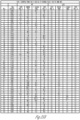

- FIGS. 25A-25H illustrate a series of tables of immunoassay plate data from a Luminex ® assay for Staphylococcus aureus (Panel A). Staphylococcus epidermidis (Panel B), Candida albicans, and Enterococcus faecalis.

- Well contents represent the controls or patient sample tested. Note that the controls for plate 1 were erroneous due to a technical error therefore the controls from plate 2 (run at the same time) were used for the assay.

- MFI median fluorescent intensity

- S.C/O signal, cut-off

- FIGS. 26A-26R illustrate a table of individual sample cell and culture data of FIGS. 25A-25H , listed in sample order, S/CO and MID immunoassay interpretation, ⁇ -defensin >1 is positive, C-reactive protein (CRP) >3 is positive, total nucleated cells (TNC >3000 is positive).

- Organism organism identified through culture at a maximum of 7 days; most samples (>95%) culture positive within 2 days